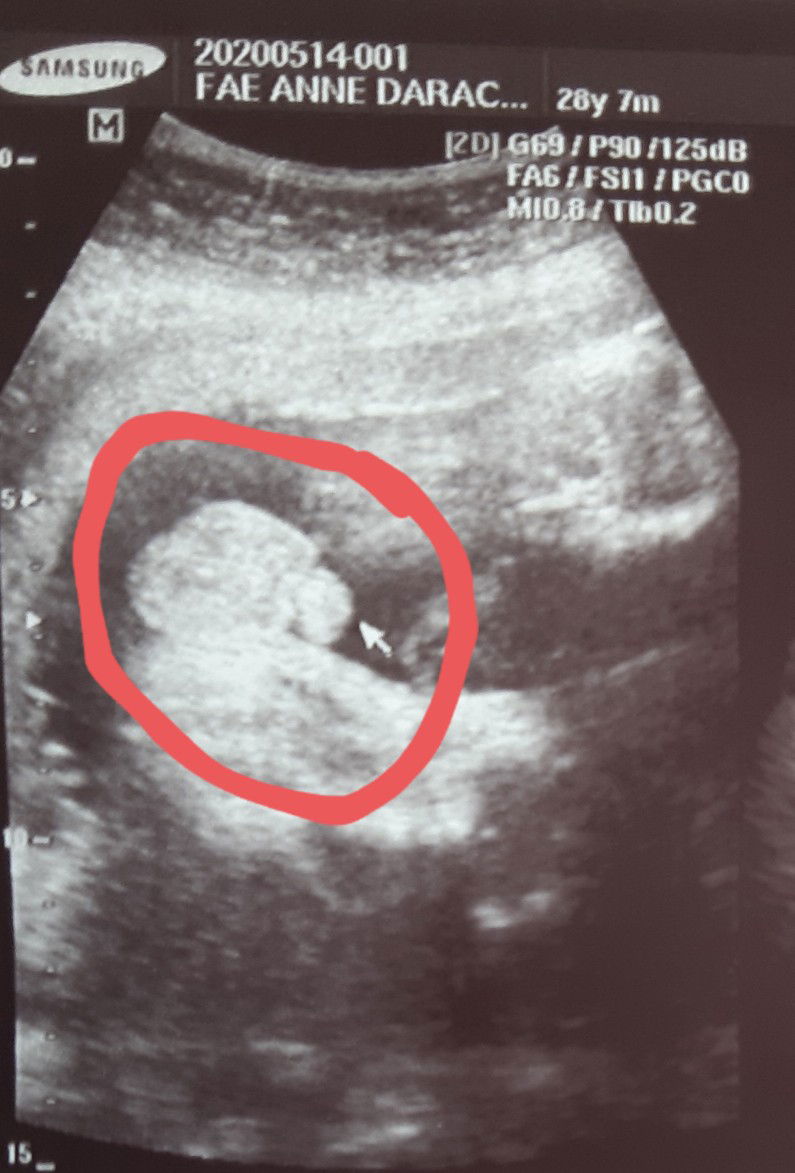

UTZ

Baby boy po kaya?

Hi! Di ko kasi talaga alam pano tumingin sa ultrasound. Kahapon kasi galing din ako sa ob ko.tapos nag utz ako sabi nung sonologist, gusto ko daw ba makita yung gender.sabi ko pwede po ba? Sabi nya tingnan ko daw may lawit, di ko talaga makita nung una, pero may konti naman ako nakita.kaya ayun boy daw.happy naman kami kasi 1st namin is girl. 19weeks po. Di po ba nasabi ng ob gender ni baby?